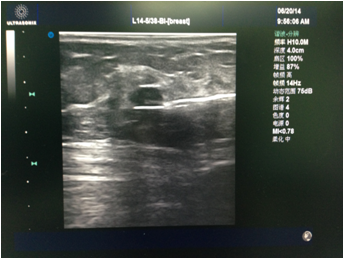

先由主刀医生行彩超检查,和患者确认及核对拟切除的目标病灶。消毒铺巾后医生在彩超引导下于表皮,手术路径及目标病灶周围注射局麻药(图1)。麻醉满意后于彩超引导下进旋切针到目标病灶下方,然后开始切除目标病灶(图2)。最后加压包扎,切除的病灶送病理检查(图3)。整个手术过程于局麻下完成,会有轻微疼痛,但一般程度不重。

图1 注射局麻药。图中黑色低回声为肿物,上方的白色条索为注射局麻药的针头。